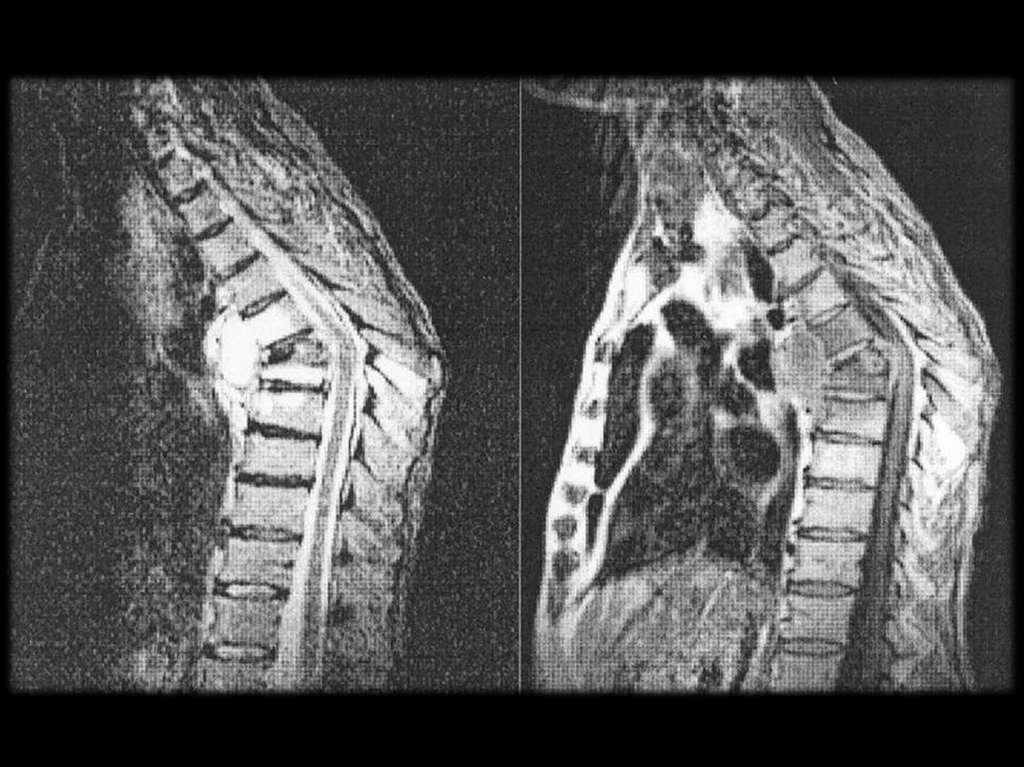

Слева — бруцеллезный спондилит поясничного

отдела позвоночника. Справа — двухсторонний

бруцеллезный сакроилеит.

Поражение позвоночника при хроническом бруцеллёзе